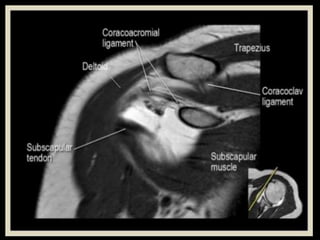

Shoulder